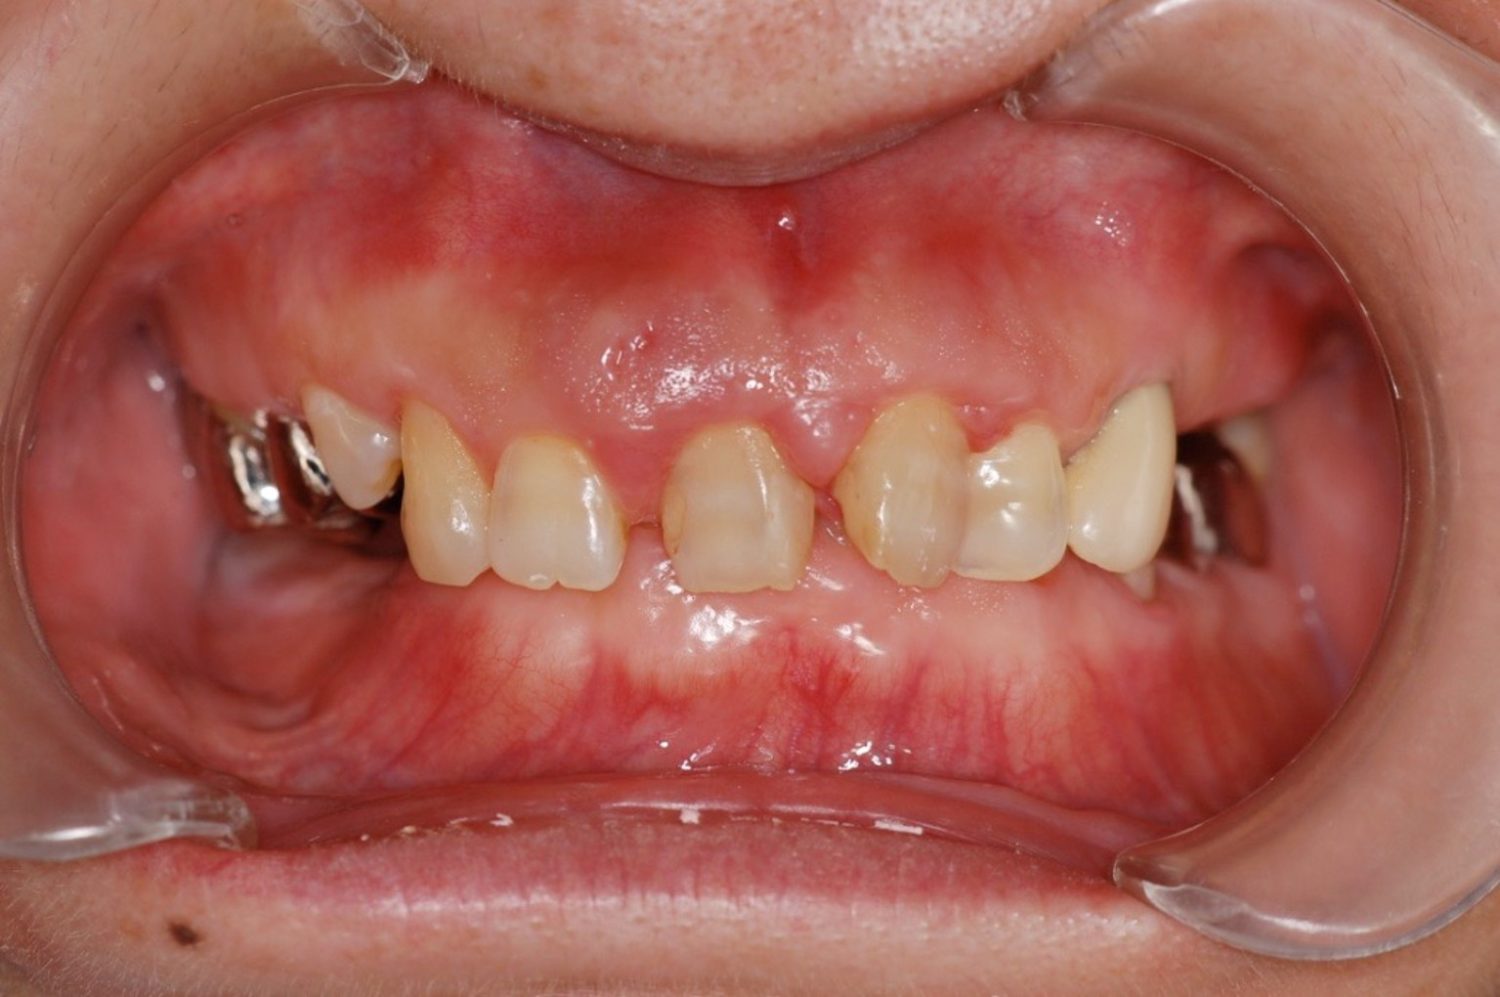

歯周病に罹患した患者さんのインプラント治療の症例①(うえだ歯科)

上田大介(うえだ歯科)

症例詳細

| 主訴 | 全顎治療希望、奥の歯茎から血が出る、綺麗で噛めるようになりたい |

| 治療内容 | 全顎的に歯周病、歯列不正が認められるため、歯周外科を含む歯周治療、矯正治療、インプラント治療、セラミックによる補綴治療後メインテナンスに移行 |

| 治療費 | 2,930,000円(税込)(インプラントすべて含む) |

| 治療期間 | 2年6ヶ月 |

| 治療回数 | 96回 |

| 想定されたリスク | 歯周病の再発、食いしばり(パラファンクション)によるセラミックの破折、歯の破折 |